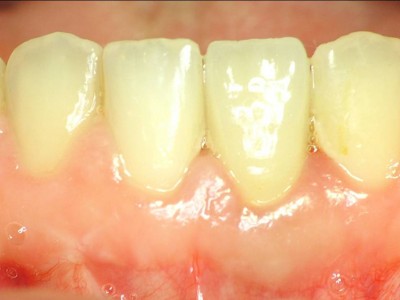

환자의 치아 모양·색상에 맞춰 맞춤 제작된 크라운을 부착해 자연스러운 심미성과 기능을 회복합니다.

A+ 임플란트의 다양한 케이스를 확인해보세요.